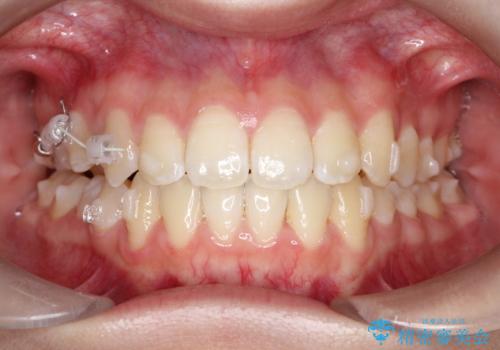

- 右上の小臼歯が大きくねじれており、噛み合わせや見た目に影響を与えている状態でした。診察の結果、インビザライン単独では十分な回転が得られにくいと判断。そのため、基本的な歯列の移動はインビザラインで行いながら、部分的にワイヤー矯正を併用するコンビネーション治療を計画しました。

まず、インビザラインで歯列全体を整えながら、スペースを確保しました。その後、部分ワイヤーを装着し、右上小臼歯の捻転を効率よく改善。ワイヤーの力を活用することで、より確実に歯の向きを整えることができました。治療後は、「しっかり噛めるようになり、見た目も自然になった」と患者様にもご満足いただきました。